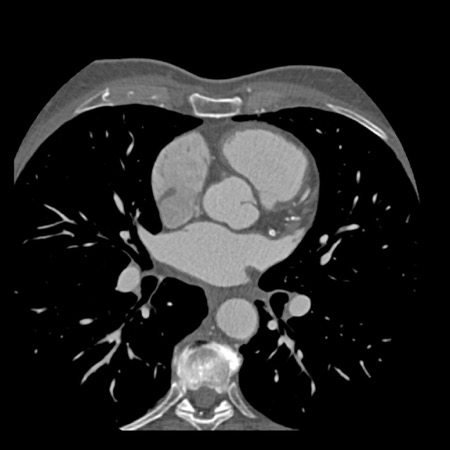

The findings are:

- Moderate (50-69%)

stenosis in the proximal LAD caused by a non-calcified plaque. - Variant of

sinoatrial (SA) nodal artery. The artery usually arises from the RCA as a second

branch after the conus artery, however in this case it arises from the LCX,

courses behind the aorta, anastomosing with the right atrium and with a small

branch supplies the SA-node of the heart. - Thrombus in the

apex of the left ventricle. - CTP was performed

in this patient. CTP showed a perfusion defect at stress imaging in the

territory of the LAD (I+), at rest no perfusion defect was visible.

This patient classifies as CAD-RADS 3/P1/I+, which means

this patient requires further investigation.